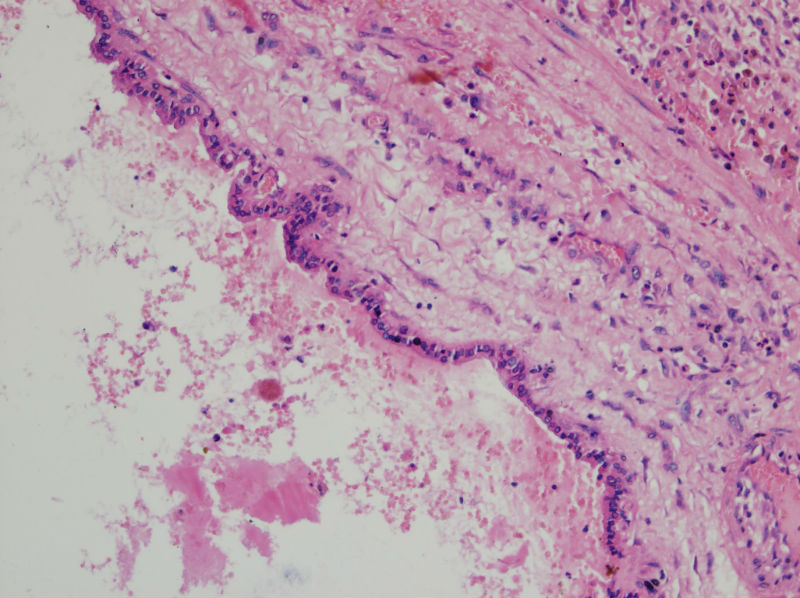

甲状腺囊肿,请老师们指教

男,44,甲状腺囊肿.直径1.5公分,内流清亮液

请教老师们:有上皮内衬的一侧为囊壁的内衬上皮,是滤泡上皮吗?肉芽组织及出血区应该是继发的反应吧?